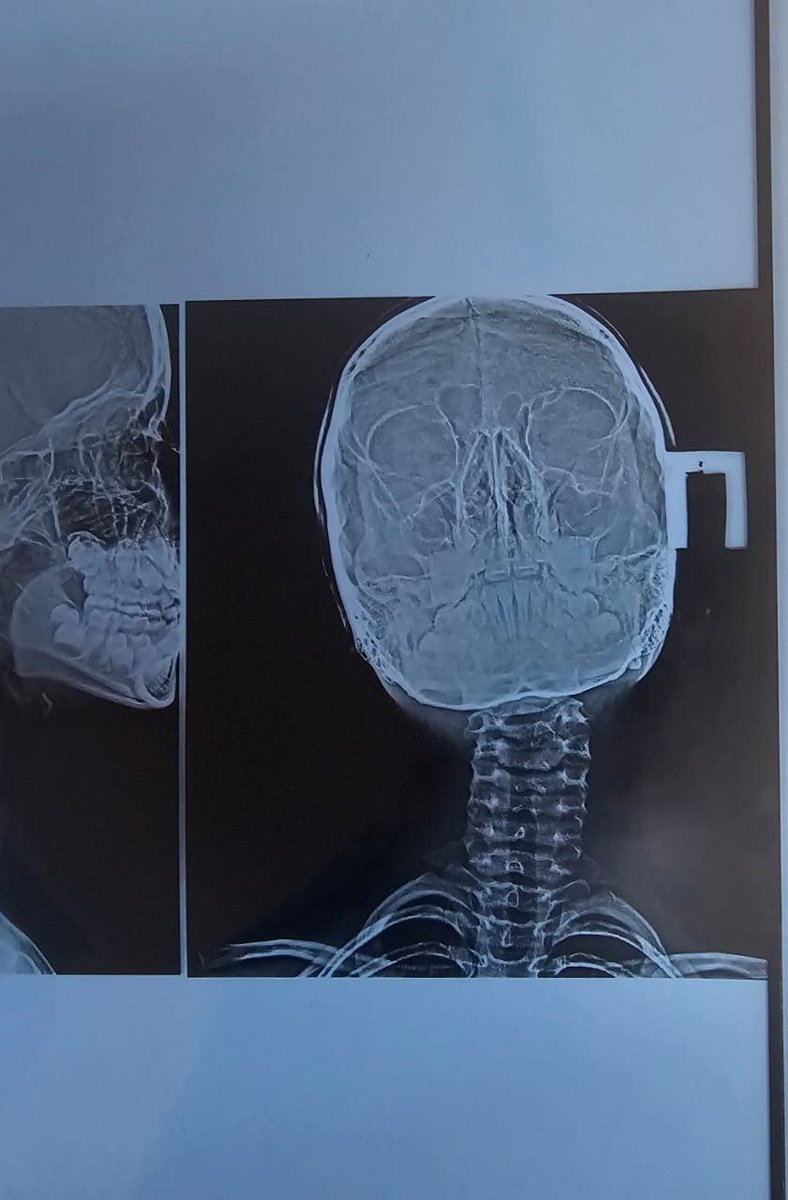

Ребёнка доставляют в травмпункт. Делают рентген, констатируют ротационный подвывих позвонка.

Мама с дочкой приехали на соревнования из другого города. На тренировке перед соревнованиями девочка совершает неудачно сложное техническое действие. Падение. Щелчок, голова набок, шея в неестественном положении.

Невозможно найти удобное положение для головы ни сидя, ни лёжа.

Голову приходится поддерживать руками. Иначе быстро появляется боль. Голова не поворачивается и не наклоняется совсем.

После сбора анализов, изучения результатов объективных методов исследования и собственного физикального обследования, я принимаю решение провести репозицию позвонка в его правильное физиологическое положение.

Ну, сказано - сделано. Манипуляция выполнена, и тут же функция восстановилась. Боли нет, голова поворачивается и наклоняется так, как нужно в рамках нормальных физиологических амплитуд.